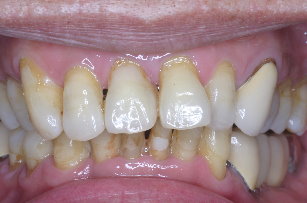

立即植牙-下顎側門齒嚴重牙周病 患者

術前、術後之比較

術前 |